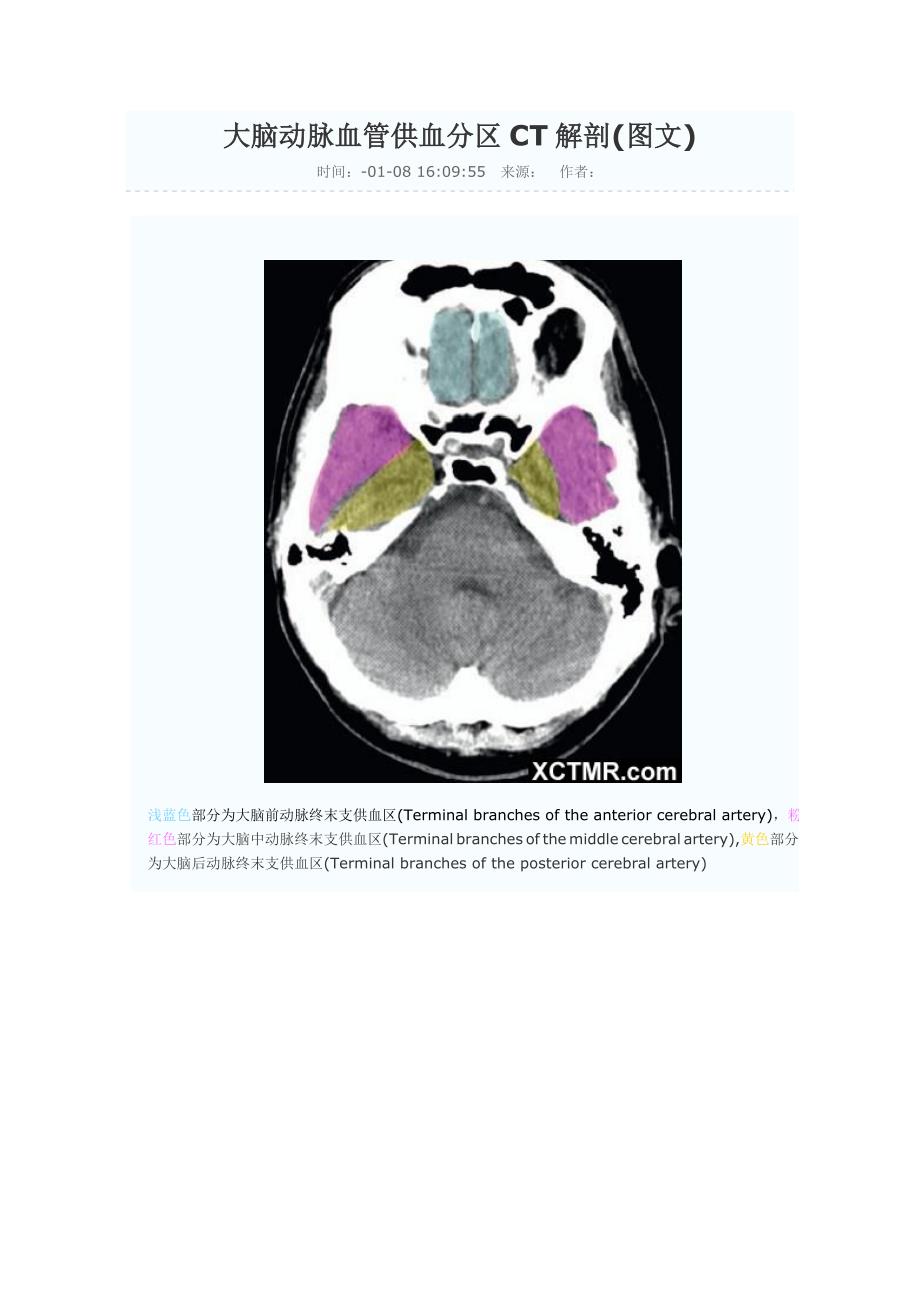

大脑动脉血管供血分区CT解剖(图文)时间:-01-08 16:09:55 来源: 作者: 浅蓝色部分为大脑前动脉终末支供血区(Terminal branches of the anterior cerebral artery),粉红色部分为大脑中动脉终末支供血区(Terminal branches of the middle cerebral artery),黄色部分为大脑后动脉终末支供血区(Terminal branches of the posterior cerebral artery)浅蓝色部分为大脑前动脉终末支供血区(Terminal branches of the anterior cerebral artery),粉红色部分为大脑中动脉终末支供血区(Terminal branches of the middle cerebral artery),黄色部分为大脑后动脉终末支供血区(Terminal branches of the posterior cerebral artery),绿色部分为脉络膜前动脉供血区(Anterior choroidal artery),浅蓝色部分为大脑前动脉终末支供血区(Terminal branches of the anterior cerebral artery),粉红色部分为大脑中动脉终末支供血区(Terminal branches of the middle cerebral artery),黄色部分为大脑后动脉终末支供血区(Terminal branches of the posterior cerebral artery),绿色部分为脉络膜前动脉供血区(Anterior choroidal artery),褐色部分为大脑前动脉深穿支供血区(Penetrating branches of the anterior cerebral artery),枣红色部分为大脑后动脉深穿支及后交通动脉供血区(Penetrating branches of the posterior cerebral artery and posterior communicating artery),浅蓝色部分为大脑前动脉终末支供血区(Terminal branches of the anterior cerebral artery),粉红色部分为大脑中动脉终末支供血区(Terminal branches of the middle cerebral artery),黄色部分为大脑后动脉终末支供血区(Terminal branches of the posterior cerebral artery),绿色部分为脉络膜前动脉供血区(Anterior choroidal artery),褐色部分为大脑前动脉深穿支供血区(Penetrating branches of the anterior cerebral artery),枣红色部分为大脑后动脉深穿支及后交通动脉供血区(Penetrating branches of the posterior cerebral artery and posterior communicating artery),亮红色部分为大脑中动脉深穿支供血(Penetrating branches of the middle cerebral artery)浅蓝色部分为大脑前动脉终末支供血区(Terminal branches of the anterior cerebral artery),粉红色部分为大脑中动脉终末支供血区(Terminal branches of the middle cerebral artery),黄色部分为大脑后动脉终末支供血区(Terminal branches of the posterior cerebral artery),绿色部分为脉络膜前动脉供血区(Anterior choroidal artery),枣红色部分为大脑后动脉深穿支及后交通动脉供血区(Penetrating branches of the posterior cerebral artery and posterior communicating artery),亮红色部分为大脑中动脉深穿支供血(Penetrating branches of the middle cerebral artery)浅蓝色部分为大脑前动脉终末支供血区(Terminal branches of the anterior cerebral artery),粉红色部分为大脑中动脉终末支供血区(Terminal branches of the middle cerebral artery),黄色部分为大脑后动脉终末支供血区(Terminal branches of the posterior cerebral artery),枣红色部分为大脑后动脉深穿支及后交通动脉供血区(Penetrating branches of the posterior cerebral artery and posterior communicating artery),亮红色部分为大脑中动脉深穿支供血(Penetrating branches of the middle cerebral artery)浅蓝色部分为大脑前动脉终末支供血区(Terminal branches of the anterior cerebral artery),粉红色部分为大脑中动脉终末支供血区(Terminal branches of the middle cerebral artery),黄色部分为大脑后动脉终末支供血区(Terminal branches of the posterior cerebral artery),浅蓝色部分为大脑前动脉终末支供血区(Terminal branches of the anterior cerebral artery),粉红色部分为大脑中动脉终末支供血区(Terminal branches of the middle cerebral artery),黄色部分为大脑后动脉终末支供血区(Terminal branches of the posterior cerebral artery),浅蓝色部分为大脑前动脉终末支供血区(Terminal branches of the anterior cerebral artery),粉红色部分为大脑中动脉终末支供血区(Terminal branches of the middle cerebral artery),黄色部分为大脑后动脉终末支供血区(Terminal branches of the posterior cerebral artery),浅蓝色部分为大脑前动脉终末支供血区(Terminal branches of the anterior cerebral artery),粉红色部分为大脑中动脉终末支供血区(Terminal branches of the middle cerebral artery), 浅蓝色部分为大脑前动脉终末支供血区(Terminal branches of the anterior cerebral artery)。